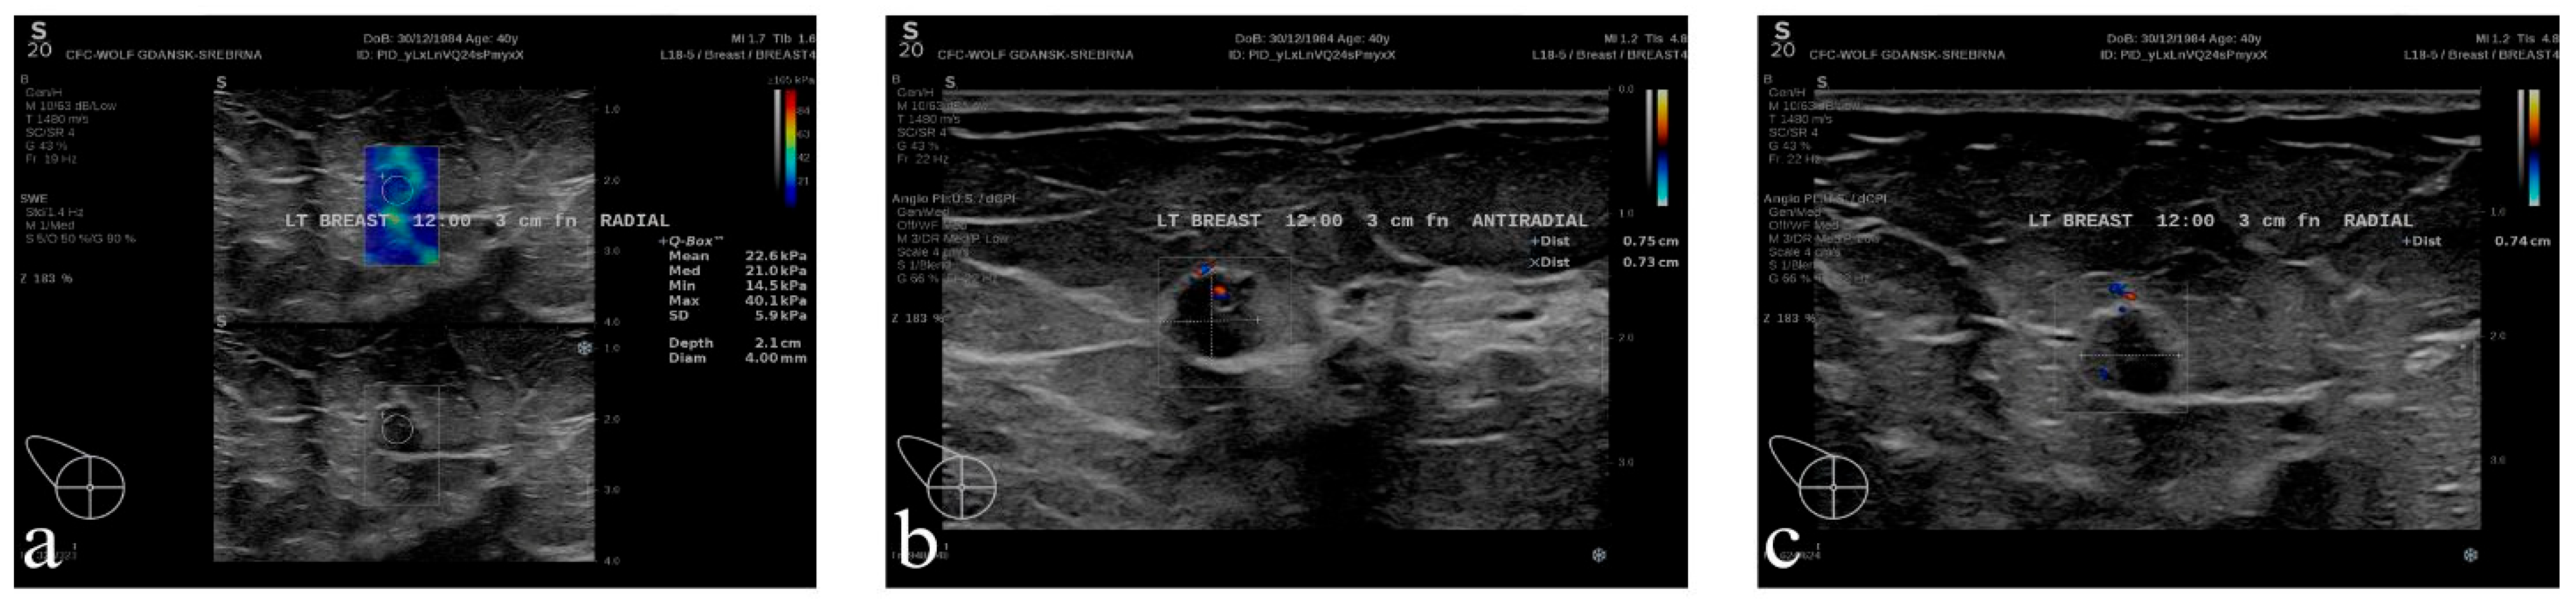

- In the third (III) session, each group of medical students (Groups A, B, C, and D) displayed a case study with clinical images of four different patients: Group A—Figure 4, Group B—Figure 5, Group C—Figure 6, Group D—Figure 7. The students were then asked to formulate an interpretation of all signs and symptoms they see.

3.5.2. Patient of Group B